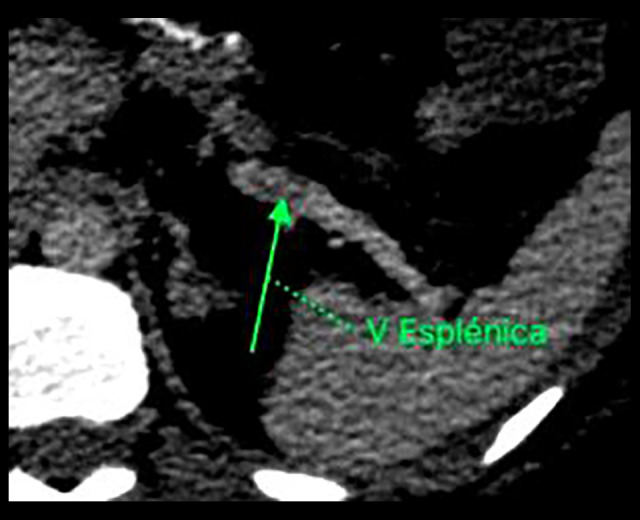

背景:自1980年以来,肥胖症的患病率增加了一倍多。因此,减肥手术率显著上升,增加了解决其并发症的需要。肠系膜静脉血栓形成是一种罕见但可能危及生命的并发症,占所有肠系膜缺血性事件的5%至15%。本病例强调了将肠系膜静脉血栓形成作为减肥手术的潜在并发症的重要性,特别是在高危患者中。病例报告一名28岁的II级肥胖女性接受了选择性腹腔镜袖式胃切除术。术后第7天,患者出现腹泻和呕吐(周末10次以上),黏膜干燥,模糊腹痛放射至腰部,口服不耐受。48小时后,没有任何改善,2024年1月7日,腹部和骨盆增强计算机断层扫描显示门静脉、肠系膜上静脉和脾静脉血管内缺损,提示血栓形成。结论:减肥手术后肠门静脉血栓形成的病因可能是多因素的。虽然静脉血栓栓塞与肥胖之间的关系已经确立,但尽管文献中已有预防措施,但关于出院后药物治疗的最佳持续时间仍存在争议。约95%的外科医生会在术后至少10至14天内使用抗凝剂,而50%的医生会将预防延长至30天,具体时间取决于个人的危险因素。虽然胃套管手术为肥胖患者提供了实质性的好处,但门脉肠系膜血栓形成的发病率不断上升,强调了积极预防和早期发现策略的重要性。

BACKGROUND The prevalence of obesity has more than doubled since 1980. Consequently, bariatric surgery rates have risen significantly, increasing the need to address its complications. Portomesenteric venous thrombosis is a rare but potentially life-threatening complication, accounting for 5% to 15% of all mesenteric ischemic events. This case highlights the importance of considering portomesenteric vein thrombosis as a potential complication in bariatric surgery, especially in patients at high risk. CASE REPORT A 28-year-old woman with grade II obesity underwent elective laparoscopic sleeve gastrectomy. On postoperative day 7, she presented with diarrhea and vomiting (over 10 episodes in a weekend), dry mucosa, vague abdominal pain radiating to the lumbar region, and intolerance to oral intake. After 48 h with no improvement, a contrast-enhanced abdominal and pelvic computed tomography scan (January 7, 2024) revealed intravascular defects in the portal vein, superior mesenteric vein, and splenic vein, suggesting thrombosis. CONCLUSIONS The etiology of portomesenteric vein thrombosis following bariatric surgery is likely multifactorial. While the relationship between venous thromboembolism and obesity is well established, debates persist regarding the optimal duration of medical therapy after discharge, despite the existing preventive measures in the literature. Some 95% of surgeons administer anticoagulants for at least 10 to 14 days postoperatively, while 50% extend prophylaxis for up to 30 days, depending on individual risk factors. While gastric sleeve surgery offers substantial benefits for patients with obesity, the rising incidence of portal mesenteric thrombosis underscores the importance of proactive prevention and early detection strategies.